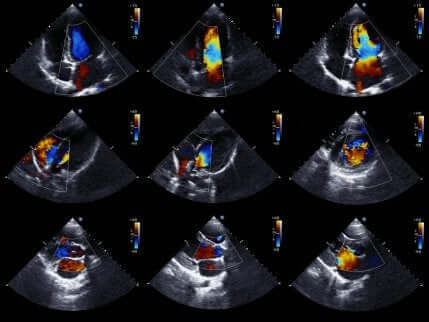

Ekkokardiogram

Som det sidste giver ekkokardiogrammer eller hjertesonogrammer medicinske fagfolk mulighed for at studere hjertet mere detaljeret.

Ekkokardiogrammet er en meget populær medicinsk test. Dette skyldes, at den giver bevægelige billeder af hjertet. Således kan den evaluere status for hjertets kamre og deres bevægelser for at bekræfte eller udelukke iskæmi.

Derudover evaluerer den også hjertestørrelse og styrke og tilstanden af væggene i hjertets kamre. Generelt er det en ikke-invasiv test, der ikke indebærer nogen risiko for patienten. Dette skyldes, at den bruger ultralyd til at få hjertebilleder.

Hvis lægen bruger denne test, udelukker fraværet af bevægelsesforstyrrelser i hjertevæggen tilstedeværelsen af iskæmi. Når alt kommer til alt, er eksistensen af bevægelsesforstyrrelser ikke unik for akut koronart syndrom. Af den grund skal testresultaterne og symptomerne vurderes i sammenhæng.